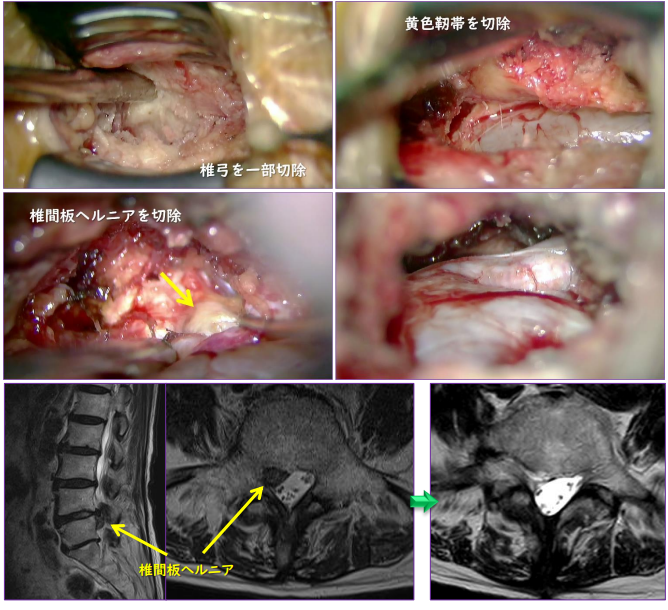

小さな皮膚切開(2.5cm)で、椎弓と呼ばれる骨の一部を削り、黄色靱帯を取り除いたのち、硬膜管や神経根を圧迫している飛び出した椎間板を取り除きます。また椎間板も摘出し、止血を確認して創部を縫合閉鎖します。手術は、手術顕微鏡を使って行います。